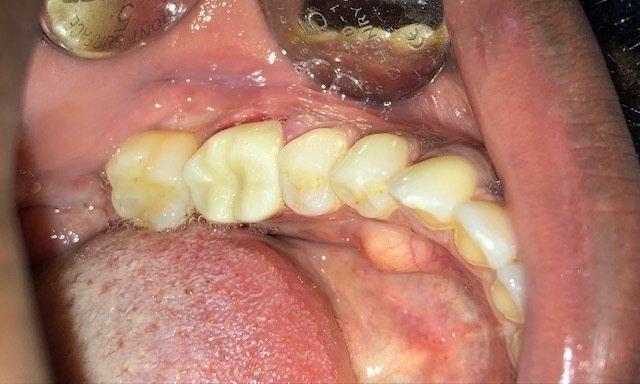

Patient with old broken filling.

This patient had an old amalgam (metal) filling that broke down and deteriorated. This is very common. When this happens, sometimes a new composite (white) filling can be placed. Depending on the size of the fracture, a full-coverage crown may be needed. An all-porcelain crown was made here in order to restore this tooth to full function.